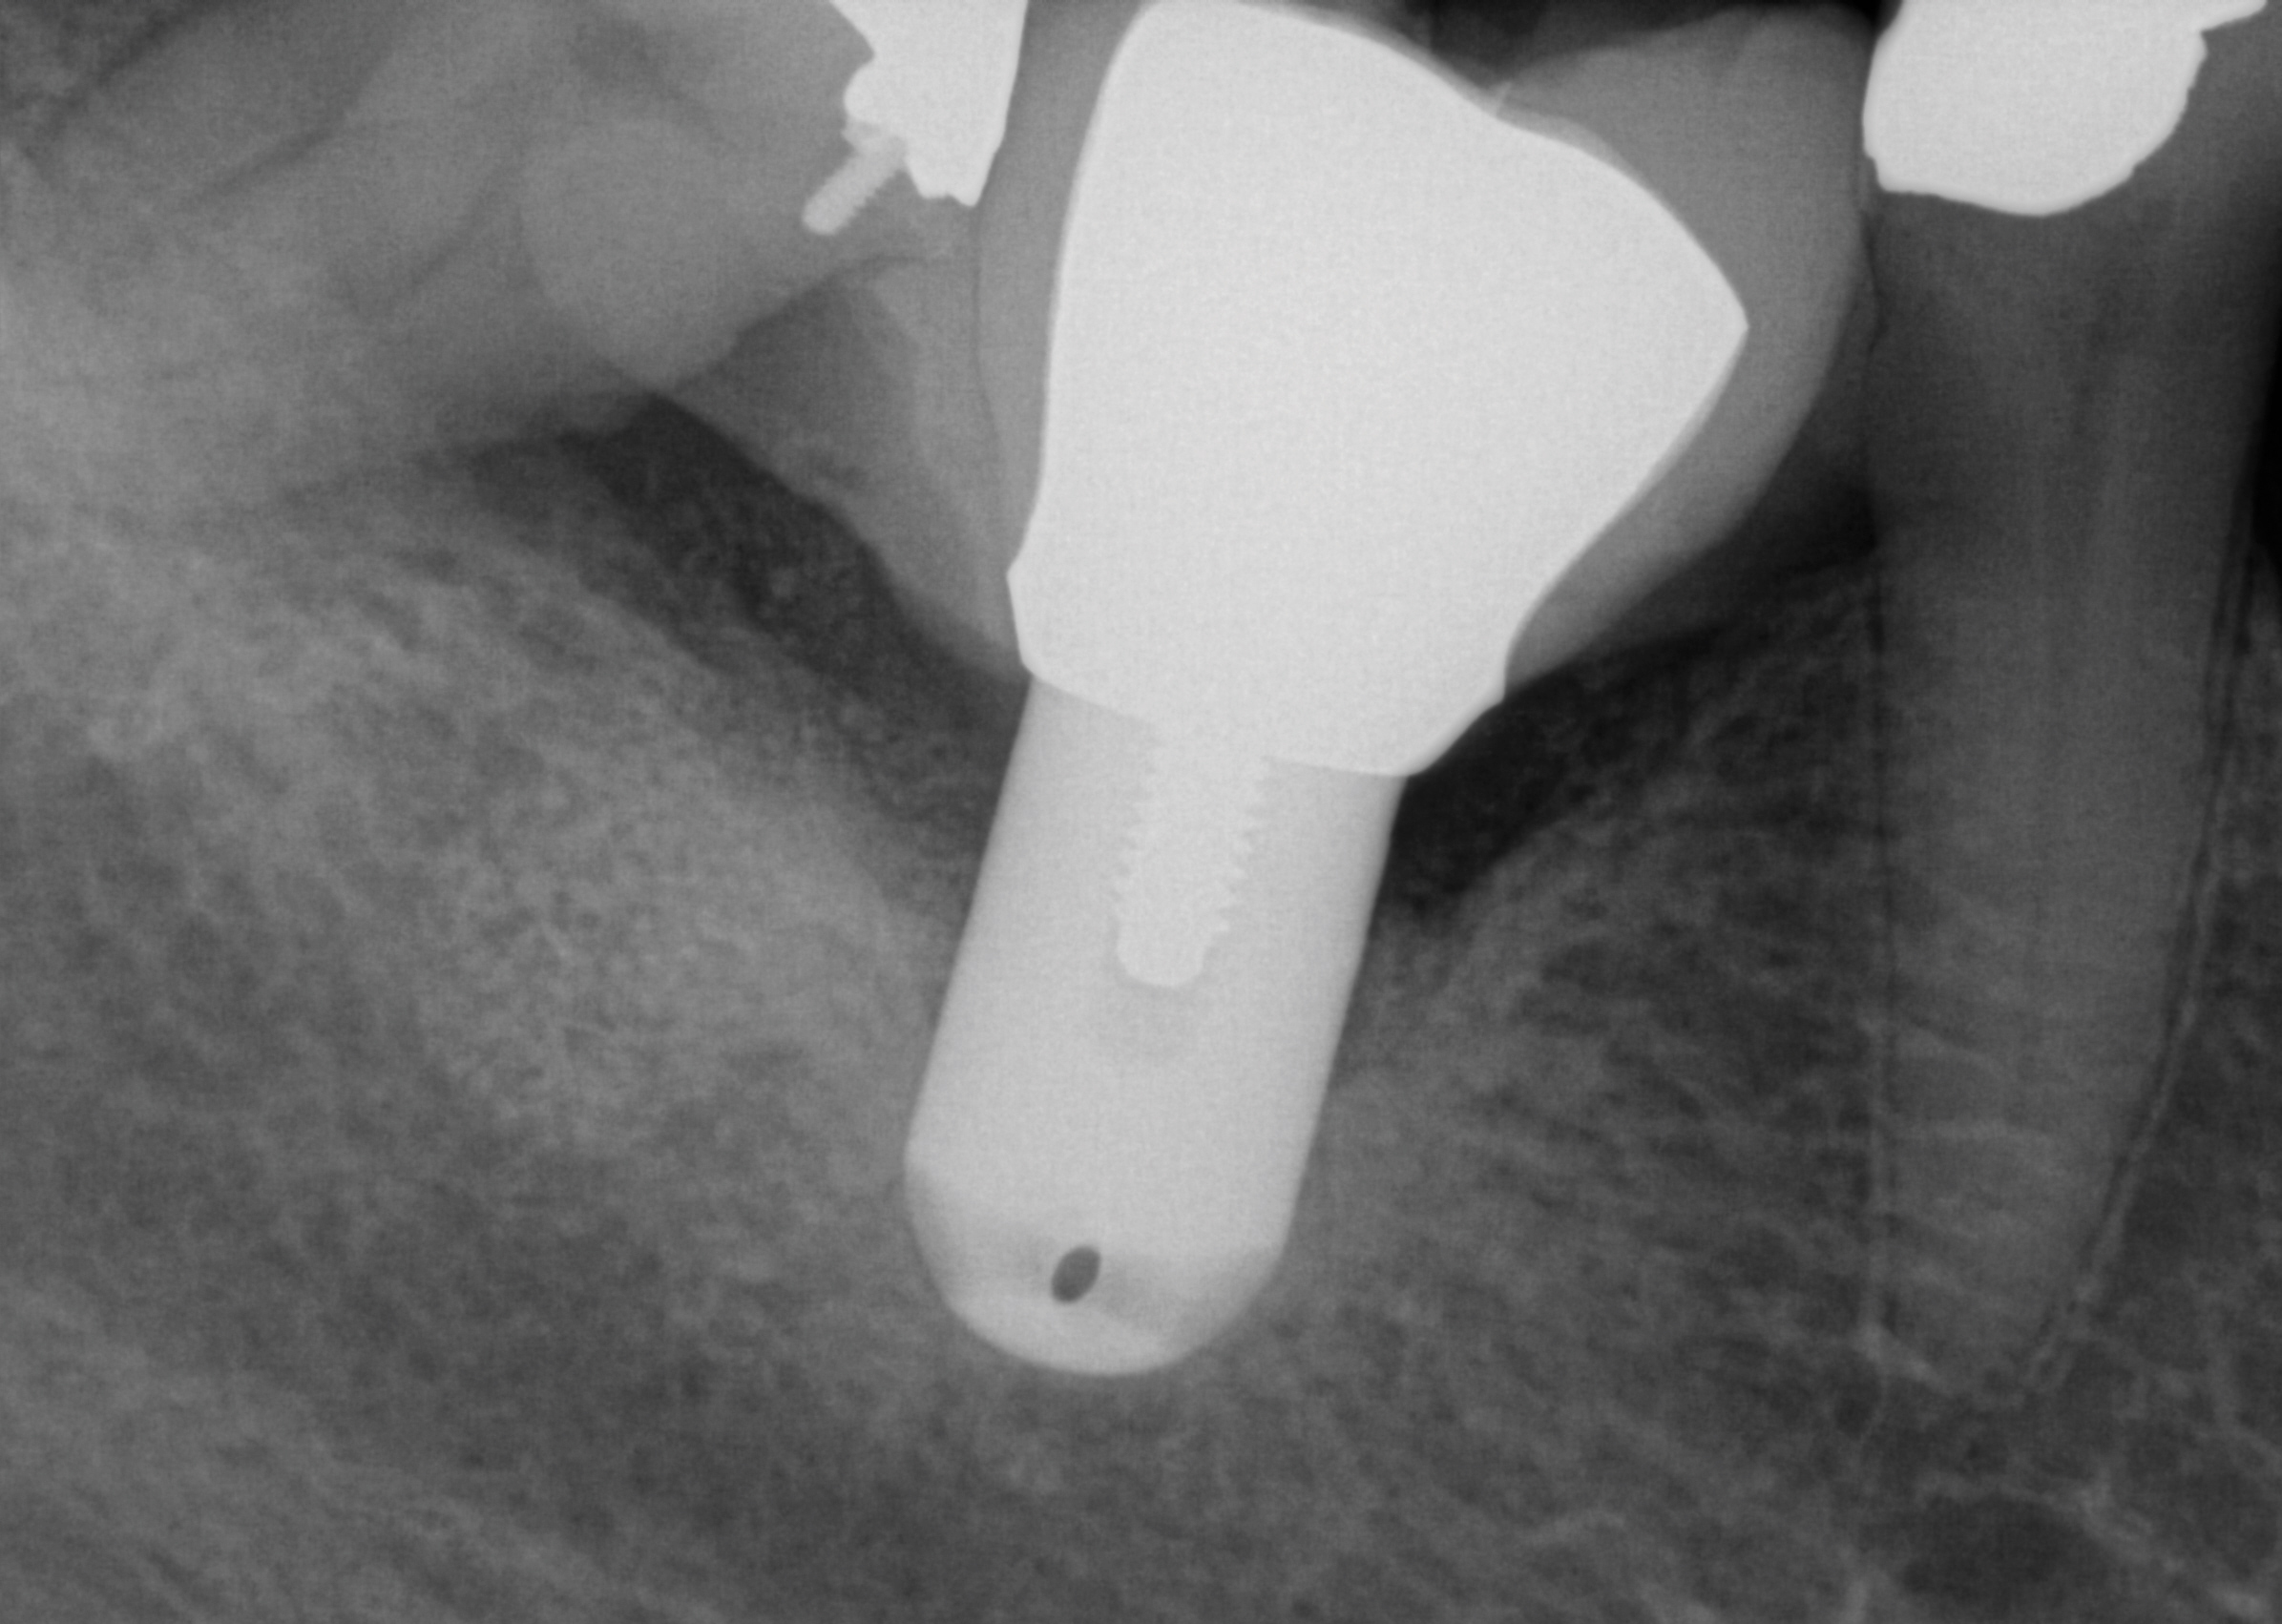

Before extracting a mandibular molar or premolar in preparation for an implant, assess the location of their roots in relation to the IAN and mental nerve, because if a nerve is juxtaposed to the roots of teeth, tooth removal has the potential to induce nerve damage. Furthermore, caution should be exercised when debriding large periapical radiolucencies, because these lesions may communicate with a nerve canal (Figure 3 and Figure 4).

Fig 3. A patient presented with intense pain in tooth No. 31. A periapical radiograph demonstrated acute apical periodontitis. It was not possible to identify the extent of the periapical lesion with respect to the inferior alveolar canal.

Figure 3

Fig 4. A CT scan was obtained. The scan demonstrated the proximity of the apical lesion to the canal. With proper preoperative planning and imaging, the tooth was successfully removed and the granulomatous tissue carefully debrided without inducing any altered nerve sensation.

Figure 4